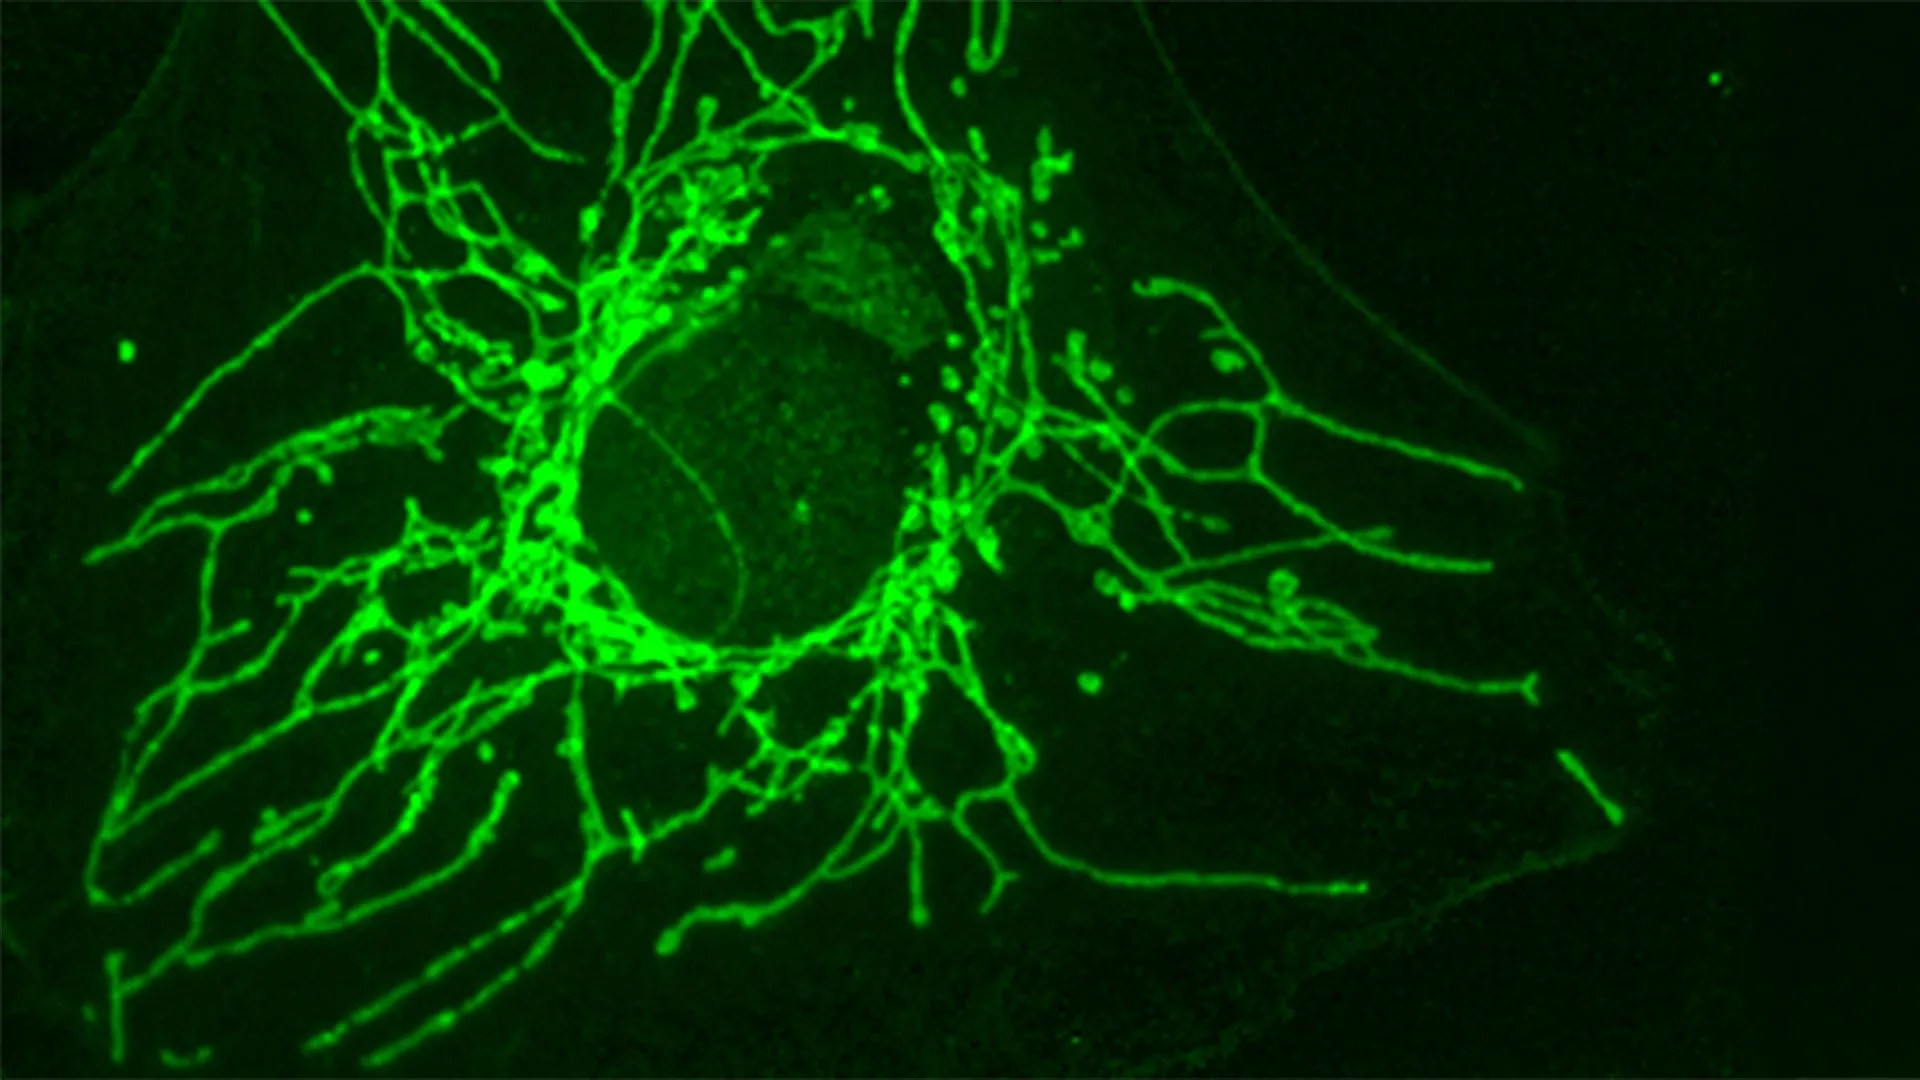

Understanding how D-cysteine exerts its detrimental effects on cancer cells was the next critical step. This mechanistic elucidation was a collaborative effort, with Professor Roland Lill and his team at the University of Marburg playing a pivotal role. Their investigations revealed that D-cysteine’s destructive power stems from its ability to interfere with a fundamental cellular process within the mitochondria—the organelles often dubbed the "powerhouses" of the cell.

Mitochondria are central to cellular respiration, generating the vast majority of adenosine triphosphate (ATP), the cell’s primary energy currency. They are also involved in numerous other critical metabolic pathways. The target identified was an essential enzyme named NFS1 (Nitrogen Fixation Siderophore 1), which is predominantly located within the mitochondria.

Professor Lill elucidated the enzyme’s crucial role: "It blocks an essential enzyme called NFS1, located in the mitochondria – the cell’s ‘powerhouses’. This enzyme plays a key role in producing iron-sulfur clusters, small structures that are indispensable for many processes such as cellular respiration, DNA and RNA production, and maintaining genetic integrity."

Iron-sulfur clusters are ancient and ubiquitous prosthetic groups found in a diverse array of proteins across all domains of life. These clusters are vital for electron transfer reactions, crucial for cellular respiration and energy production; they participate in various enzymatic reactions, including those involved in DNA synthesis and repair; and they are integral to maintaining the structural integrity and function of numerous metabolic enzymes. When NFS1 is inhibited by D-cysteine, the cell’s ability to synthesize these indispensable iron-sulfur clusters is severely compromised.